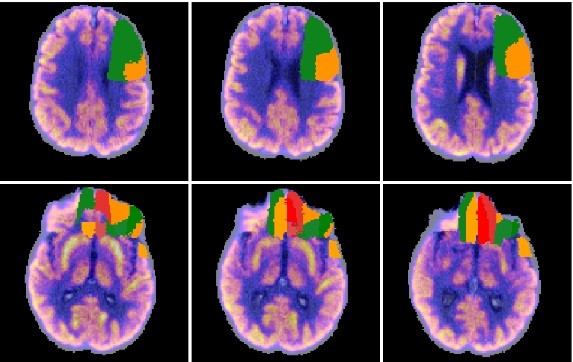

La compañía biotecnológica gallega Qubiotech Health Intelligence, dedicada al desarrollo y comercialización de software para mejorar el diagnóstico y seguimiento de enfermedades neurodegenerativas, ha cerrado una ronda de financiación para consolidar su crecimiento y preparar su internacionalización.

La compañía, que utiliza el procesamiento de imágenes basado en Inteligencia Artificial para el desarrollo de diagnósticos, ha anunciado que de esta manera han entrado en su accionariado los fondos especializados Sémola Tech Ventures y Nowture.